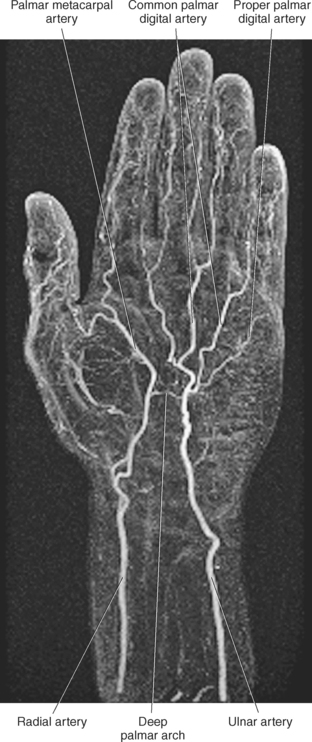

The terminal branches of the radial and ulnar arteries form the palmar arches of the wrist and hand. These arches emit branches that serve the wrist, palm, and digits (Figures 9.144 and 9.145). The palmar carpal arch or network is formed by the palmar carpal branches from the radial and ulnar arteries, the anterior interosseous artery, also a branch of the ulnar artery, and a recurrent branch from the deep palmar arch. These vessels supply the carpal bones and joints (Figure 9.144, A and C). The dorsal carpal arch or network is formed by dorsal carpal branches of the radial and ulnar arteries. The dorsal carpal arch also receives contributions from the anterior and posterior interosseous arteries. The arch lies close to the dorsal surface of the carpals and gives rise to three dorsal metacarpal arteries and branches that supply the distal regions of the ulna and radius, carpal bones, and intercarpal joints (Figure 9.144, A and C). The superficial palmar branch of the radial artery anastomoses with the superficial palmar branch of the ulnar artery to form the superficial palmar arch. This arch gives rise to three common palmar digital arteries that anastomose with the palmar metacarpal arteries from the deep palmar arch (Figure 9.144, A and C). The deep palmar arch is formed by deep palmar branches of the radial and ulnar arteries and is located approximately 1cm proximal to the superficial palmar arch. The deep palmar arch also gives rise to a recurrent branch that anastomoses with the palmar carpal branches of the radial and ulnar arteries (Figure 9.144, A).